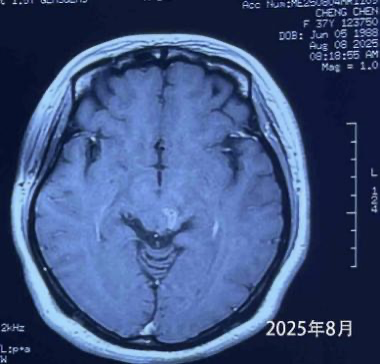

More than four years later, the patient remains in excellent condition, leading a normal life and working without restrictions. Dr. Wang emphasized the importance of regular MRI follow-ups. If small recurrences are detected, timely CyberKnife treatment can control progression. At her latest MRI check in August, the tumor had significantly shrunk.